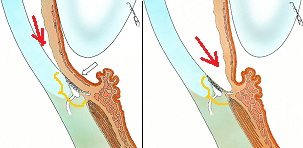

黄斑円孔の手術に関しては、?で記載しましたが、簡単におさらいすると、目の中に器械をいれて、内境界膜という網膜の表層の膜を剥離し、網膜を柔らかくします。その後、目の中に空気を入れてうつ伏せをすることで、円孔の周囲の網膜を浮力で引き寄せて、穴を閉じる。という方法です。

なくなってしまった中心部(黄斑部)の網膜を元に戻すのではありません。

周りの網膜を引き寄せて、穴を閉じ、中心部の網膜の代役をさせるのです。

?黄斑円孔で、赤の部分の網膜が硝子体に引っ張られて断裂し、無くなってしまうと、視野の中心部が欠損、見たい部分が見えなくなってしまいます。

?手術の効果で、青や緑の網膜を中心部に引き寄せます。

?青の部分の網膜が、視野の中心部の視界を担うようになります。